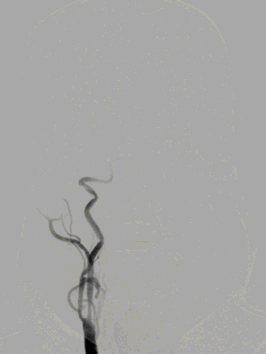

术前影像学检查

颅脑CT ASPECTS 9分。

Cranial Cervical & Aortic arch MRA。

Cranial DWI:右侧壳核、侧脑室旁小片状+皮层点状弥散受限。

Cranial SWI:SVS+AHVs RMCA M1长条血栓。

T2 Flair:丰富的高信号血管征(HVS)。

RICA C1闭塞,来自RACA丰富的软膜支代偿。

RVA超选造影仍可见后循环丰富的软膜支向右侧颞叶代偿供血。

FlowGate 2同轴Catalyst 7、Synchro 2多次调整后穿过C1起始闭塞处,MicroPort Pioneer 2.5mm×20mm球囊C1起始处缓慢扩张,顺球囊Catalyst 7穿过闭塞段,继续向前推进FlowGate 2失败, Catalyst 7 C1抽吸出长条血栓。

Catalyst 7 C1抽吸出大负荷血栓。

术后RICA造影 :mTICI 3级。